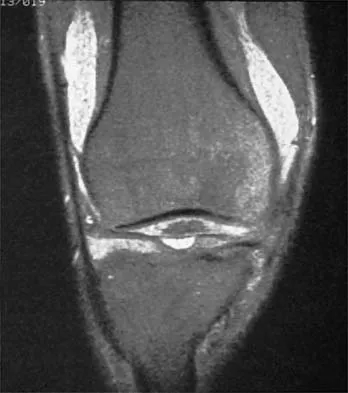

Which of the following primary prognostic factors best predicts the outcome of the knee lesion shown in Figure 22?